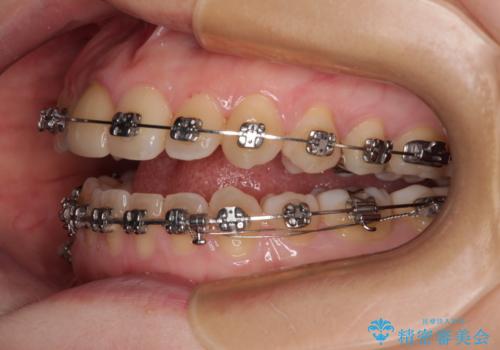

【モニター】後戻りでできた隙間 ワイヤー装置での再矯正

- 学生時代に行った抜歯矯正の後戻りで、隙間ができてしまったことを気にして来院された患者様です。

マウスピース矯正を検討されていましたが、後戻りの隙間が非常に大きく、奥歯を前方に移動させる必要があるため、ワイヤー装置にて矯正治療を行うこととしました。

舌の突出癖が非常に強く、その影響で隙間ができてしまったので、舌のトレーニングをしっかりと行っていただきました。

上顎歯列は歯の移動量が少なかったため、セラミッククラウンは装置を装着せずに治療を終えることができました。